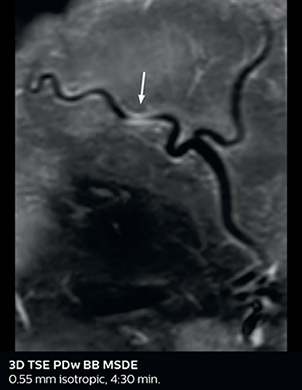

Giant cell arteritis

The 3D TSE T1w black blood MSDE sequence with fat suppression has an isotropic 0.8 mm voxel size and sagittal oblique and axial reformats are made. The images show superficial temporal artery thickening and peri-arterial fat infiltration. The 3D TSE PDw black blood MSDE with fat suppression has 0.55 mm isotropic voxels. The images shows focal involvement of the frontal branch of the superficial temporal artery.

3D TSE T1w BB MSDE

3D TSE PDw BB MSDE